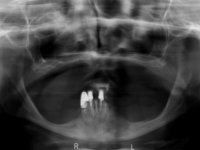

After clinical and radiological evaluation several rehabilitation plans were discussed with the patient. It was decided to extract the remaining lower teeth and do an overdenture retained by two dental implants with the locator attachement system to achieve a better retention and stabilization of the lower denture.

Two dental implants were planned in the CBCT scan, in the area of the inferior canines. The dental extractions were performed and, simultaneously, the alveolar crest was flattened and the implants were placed. Three issues were considered while implant placement: parallelism of the axis, same height of the implant’s neck, and same position in the coronal plan. This 3D insertion is essential to have a good retention of the overdenture in the future. Patient’s removable denture was fixed in the dental lab, to include the extracted teeth, and a soft-tissue relining was done over the healing abutments. After the osseo-integration period, a first impression was done with an open-tray and a doble-mix technique. This dental impression allowed the production of screwed wax-rims and an individual tray for a functional impression. A second impression, final, was done with an individual tray with a monophasic silicone. The occlusal wax-rims were correct in the mouth according to the full denture guidelines. Special care was taken with the occlusal vertical dimension and the support in the soft-tissues. A silicone bite registration material was used to better defined the intermaxillary relations. Teeth set-up was done in the dental lab with the selected tooth color. Due to the fact that the base was screwed to the dental implants, the teeth set-up was functionally evaluated in the mouth. Another silicone bite registration material was used to allow final occlusal adjustments. Finally, the locators were screwed and the retention nylons were selected according to the patient needs.